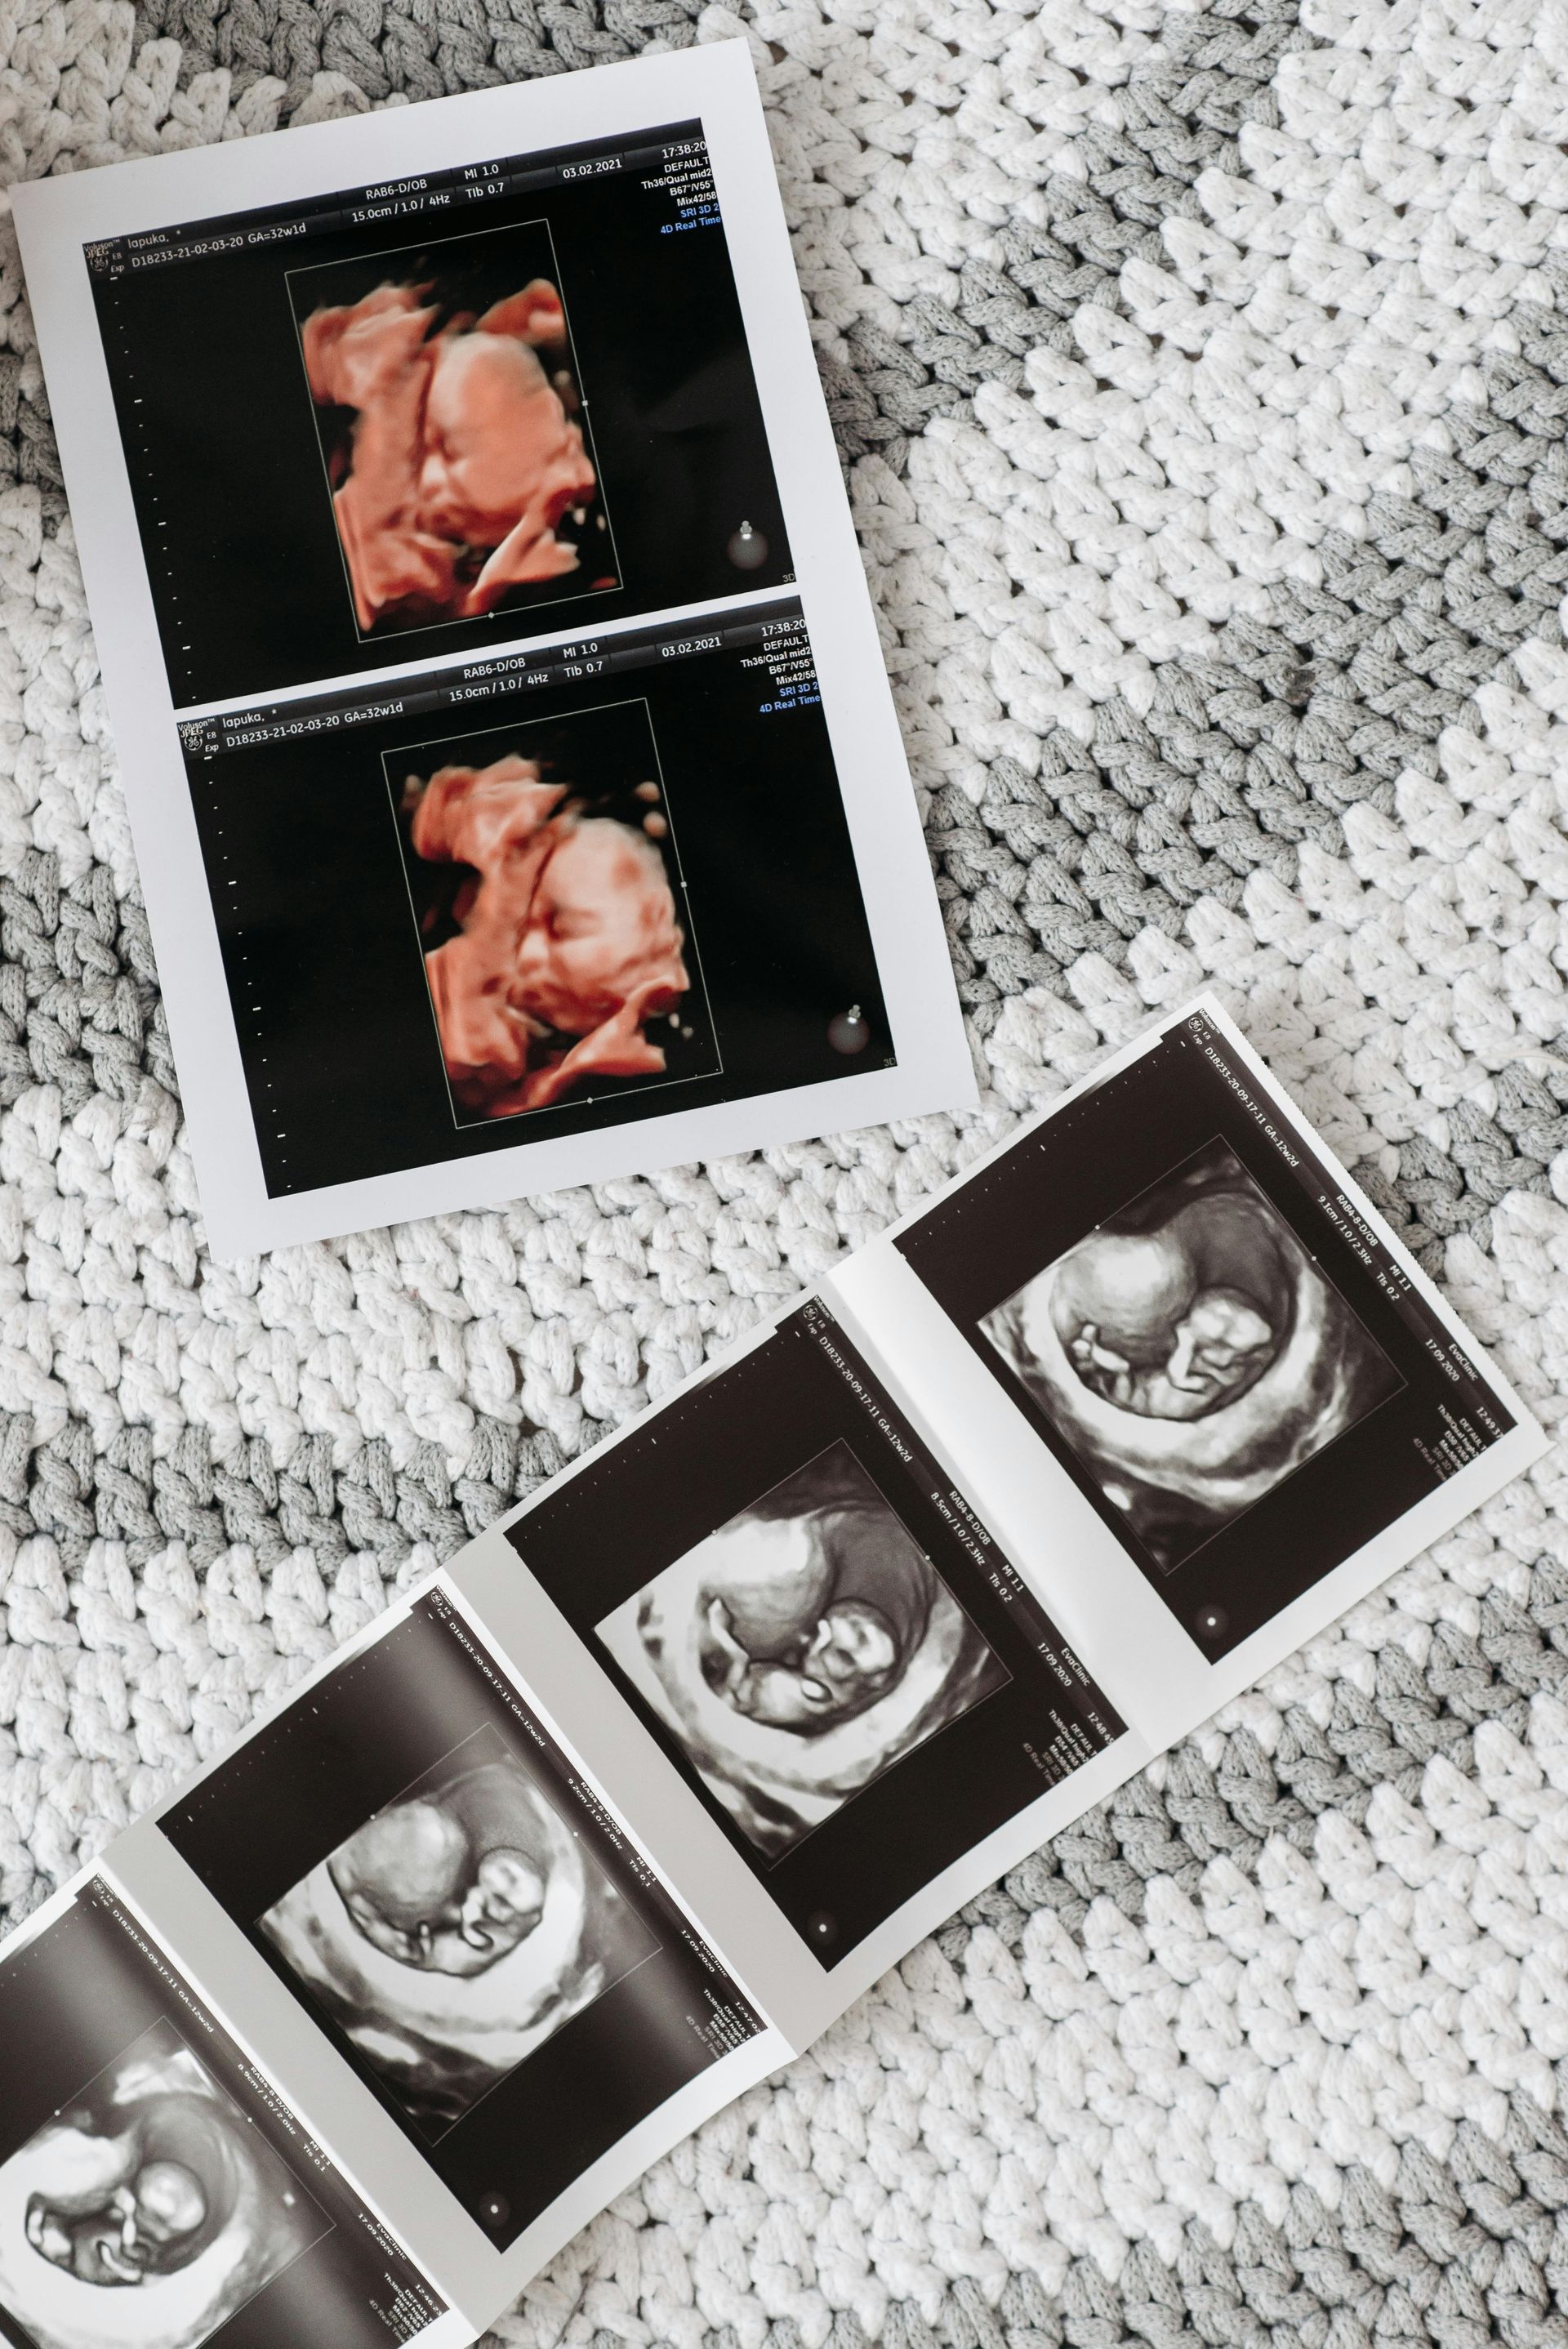

The Premier $75

A 15 min 2D peek to check on baby and hear the heartbeat. This session is available at any gestation, 9-40 weeks! Includes digital and printed black and white images.